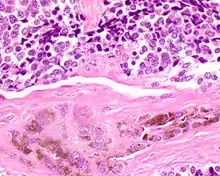

| A bone resection sample showing the pigmentation below the surface in a melanotic neuroectodermal tumor of infancy | |

The tumor is usually very well circumscribed but not encapsulated. There are two cell types present (biphasic), arranged in alveolar or tubular configurations.

There are centrally located, small, darkly staining cells comprising the majority of cells. These cells have a fibrillary cytoplasm surrounding round nuclei with coarse and heavy nuclear chromatin. These cells are surrounded by much larger polygonal cells that have open nuclear chromatin and abundant opaque cytoplasm that has granular melanin pigment.

There is usually no hemorrhage, necrosis or increased mitoses.[1][4]